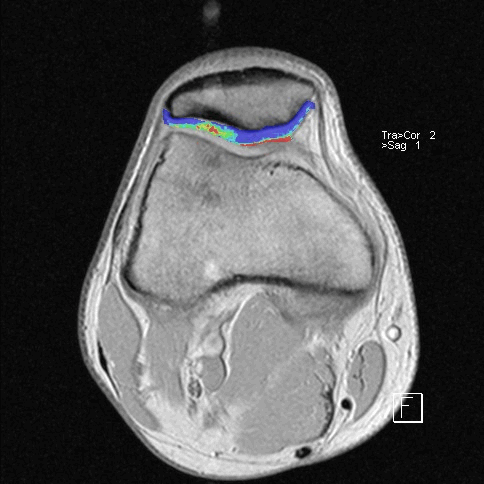

После операции лучезапястный сустав фиксировался иммобилизационной повязкой сроком на 4 недели. По окончанию срока иммобилизации пациентке была рекомендована постепенная разработка лучезапястного сустава, исключающая осевые нагрузки. Через 6 недель с момента операции пациентке было выполнено МРТ исследование для осуществления контроля положения восстановленной связки (рис. 5).

Рис. 5. МРТ исследование правого лучезапястного сустава. На МРТ сканах во фронтальной плоскости: 1) отмечается восстановление пространства между ладьевидной и полулунной костями, отчетливо видна связка; верифицируется биодеградируемый пин и якорный фиксатор в ладьевидной кости; 2) отмечается синовит лучезапястного сустава и отсутствие отека костной ткани ладьевидной кости